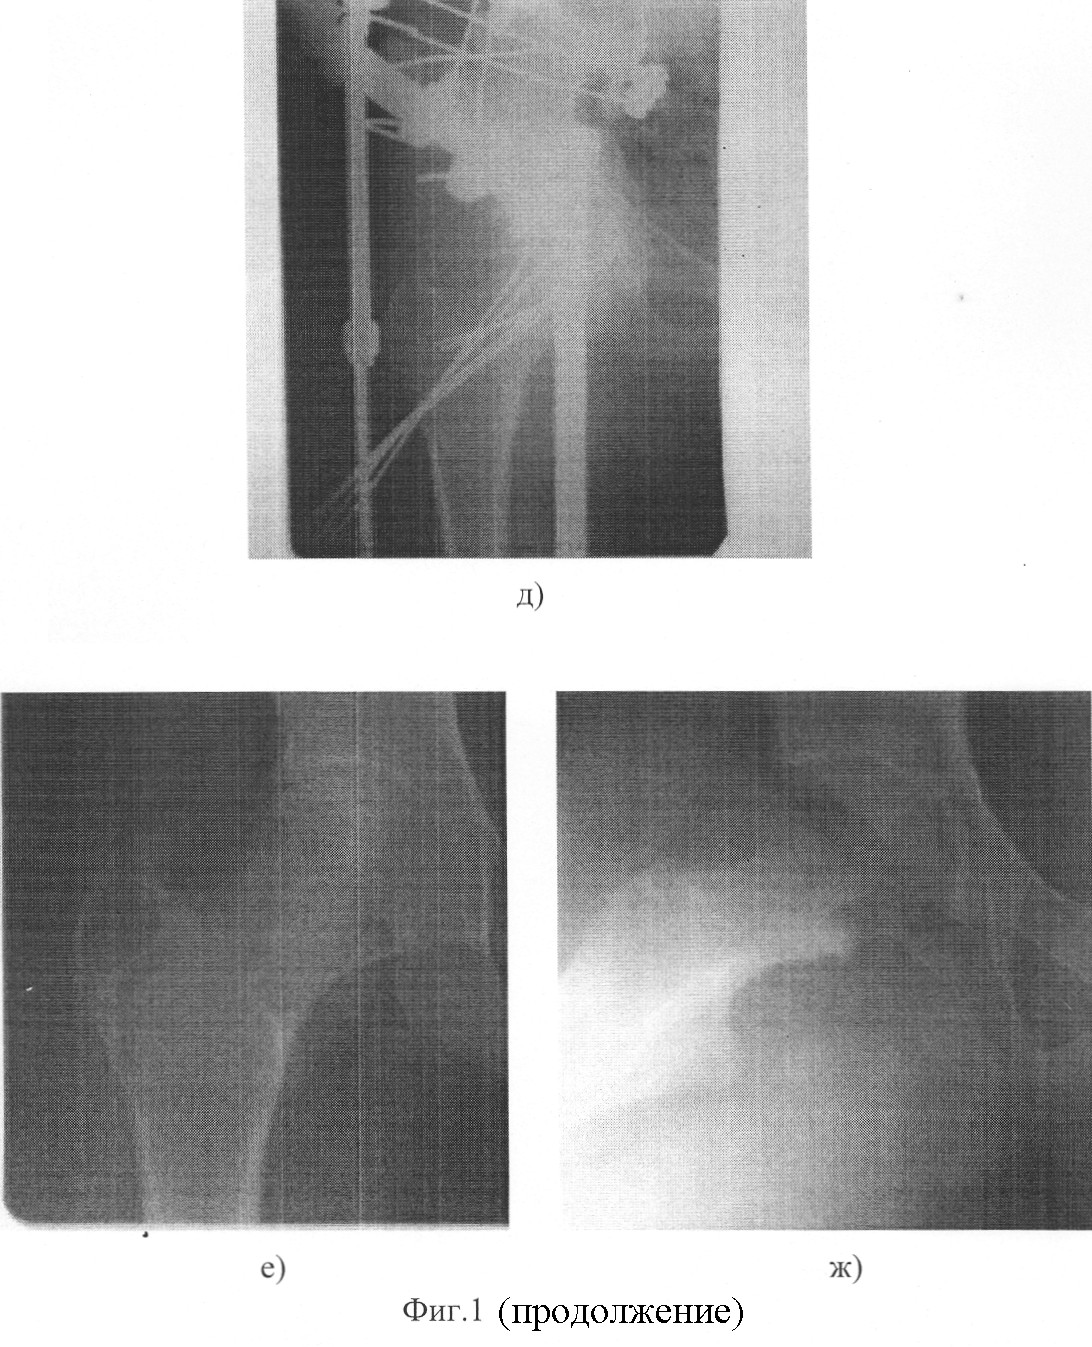

Фоторентгенограммы больного К. произведены на чертеже,

где а, б – до лечения;

в, г – фиксация эпифиза трансацетабулярно проведенными спицами;

д – остеосинтез бедренной и подвздошной костей аппаратом Илизарова с созданием условий разгрузки в тазобедренном суставе;

е, ж – отдаленный результат.

Больной К., 14 лет поступил в клинику с диагнозом: юношеский эпифизеолиз головки бедренной кости; рентгенологически – смещение эпифиза кзади 60 градусов.

В ходе операции, согласно предложенному способу, после центрации эпифиза относительно вертлужной впадины путем установки бедра в положение максимальной наружной ротации, полного разгибания и приведения 15 градусов, его фиксировали четырьмя трансацетабулярно введенными спицами. После этого, сгибанием до 60, внутренней ротацией на 70 и отведением на 15 градусов, выполнили репозицию эпифиза и шейки, которые фиксировали введенным по оси шейки пучком спиц. Удалив трансацетабулярно введенные спицы, бедро вывели в положение нормокоррекции и с применением аппарата Илизарова произвели остеосинтез подвздошной и бедренной костей с созданием условий разгрузки в тазобедренном суставе.